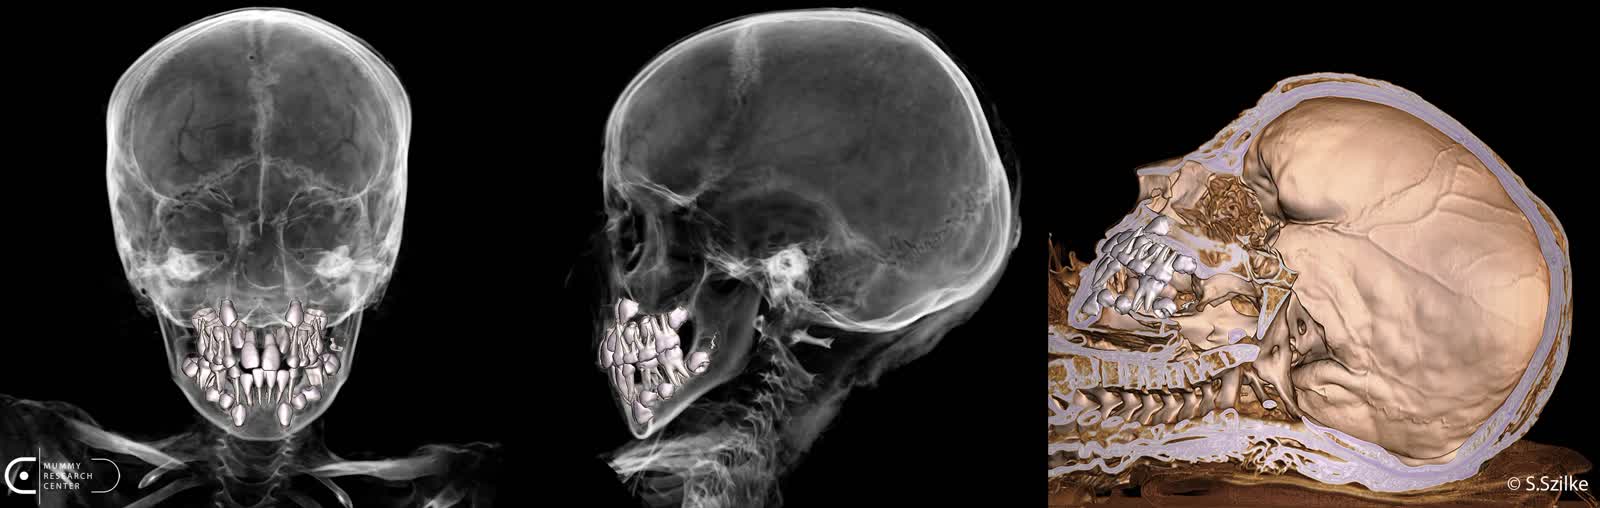

– Mieliśmy pełną świadomość, iż od 2000 lat nikt tego wnętrza nie oglądał. Doskonale zachowany kościec, co było dla mnie też sporym zaskoczeniem. Wszyscy znamy obraz mumii z zewnątrz, jak one wyglądają. Natomiast to, iż kryją w środku tak doskonale zachowane struktury kostne było dla mnie dużym pozytywnym zaskoczeniem. Tutaj akurat, w tym konkretnym przypadku, również tkanki miękkie były zachowane w taki sposób, mówię o skórze, iż można było bez problemu rozpoznać płeć chłopca.

– Dzięki dotychczas przeprowadzonym badaniom jesteśmy w stanie dokładnie zrekonstruować ciało zmumifikowanego chłopca – mówi prezes Fundacji Mummy Research Center Marzena Ożarek-Szilke. – Jesteśmy w stanie wydrukować szkielet, jesteśmy w stanie wydrukować każdy element mumii w tej chwili. Już zrobiliśmy wirtualną autopsję, można ją zobaczyć na YouTube Fundacji Mummy Research Center. Poza tym jeszcze takie badania pozwalają na stworzenie, powiedzmy, takiego korpusu, wydrukowanie mumii, na którą będzie można zdjąć kartonaż. Bo teraz największym wyzwaniem, jakie stoi przed nami, to jest konserwacja tej mumii, dlatego iż kartonaż jest w bardzo złym stanie. On został w pewnym etapie przechowywania muzealnego posklejany taśmą, taką zwykłą taśmą malarską, która jest naklejana bezpośrednio na malowidła.